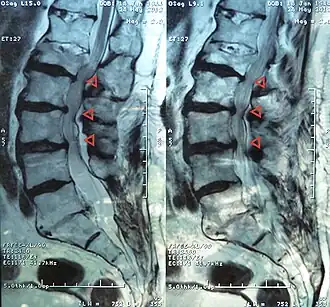

Estenosis de canal a nivel L4-3-2-1 | ||

La estenosis espinal es el estrechamiento del canal de la columna cervical (cuello) o lumbar (espalda) que causa compresión de la médula espinal y de las raíces del nervio o radiculopatía.[1]

El término estenosis medular lumbar incluye la estenosis del canal espinal, el receso lateral y los agujeros o forámenes intervertebrales siendo más común en los niveles L2 a L5 y constituye una de las causas más comunes de dolor en la espalda y en las extremidades inferiores por opresión de la médula y de las raíces nerviosas espinales.[2]